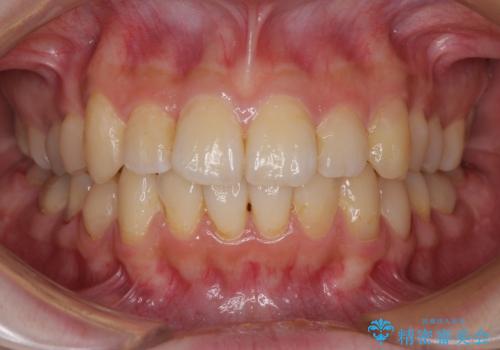

デコボコ歯列をきれいに インビザラインによる矯正治療

- 上下歯列全体のデコボコを気にして来院された患者様です。

主に下顎歯列全体の後方移動とIPR(歯と歯の間を削る)によってデコボコが解消するように設計し、インビザラインにより治療を行うこととしました。